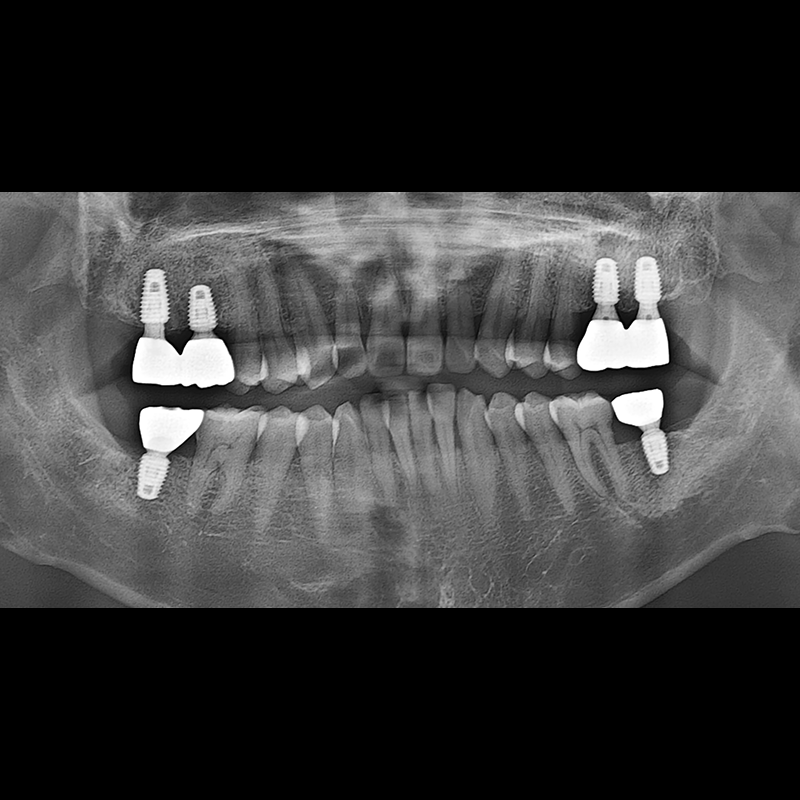

BEFORE AFTER

种植牙前后的照片 2025.05.30

在缺失的牙齿部分和难以挽救的牙齿位置植入了种植牙。